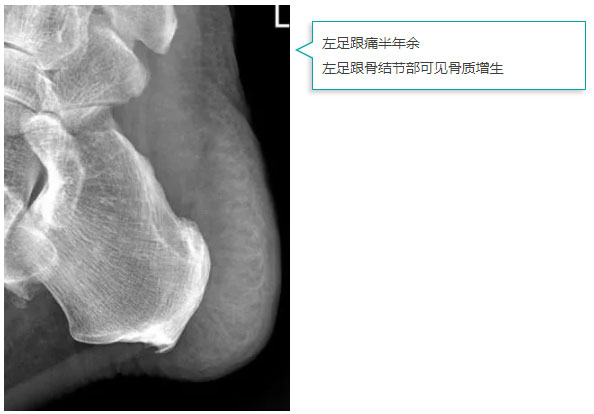

图像质量

*以上图像来源:西安医学院附属红会医院